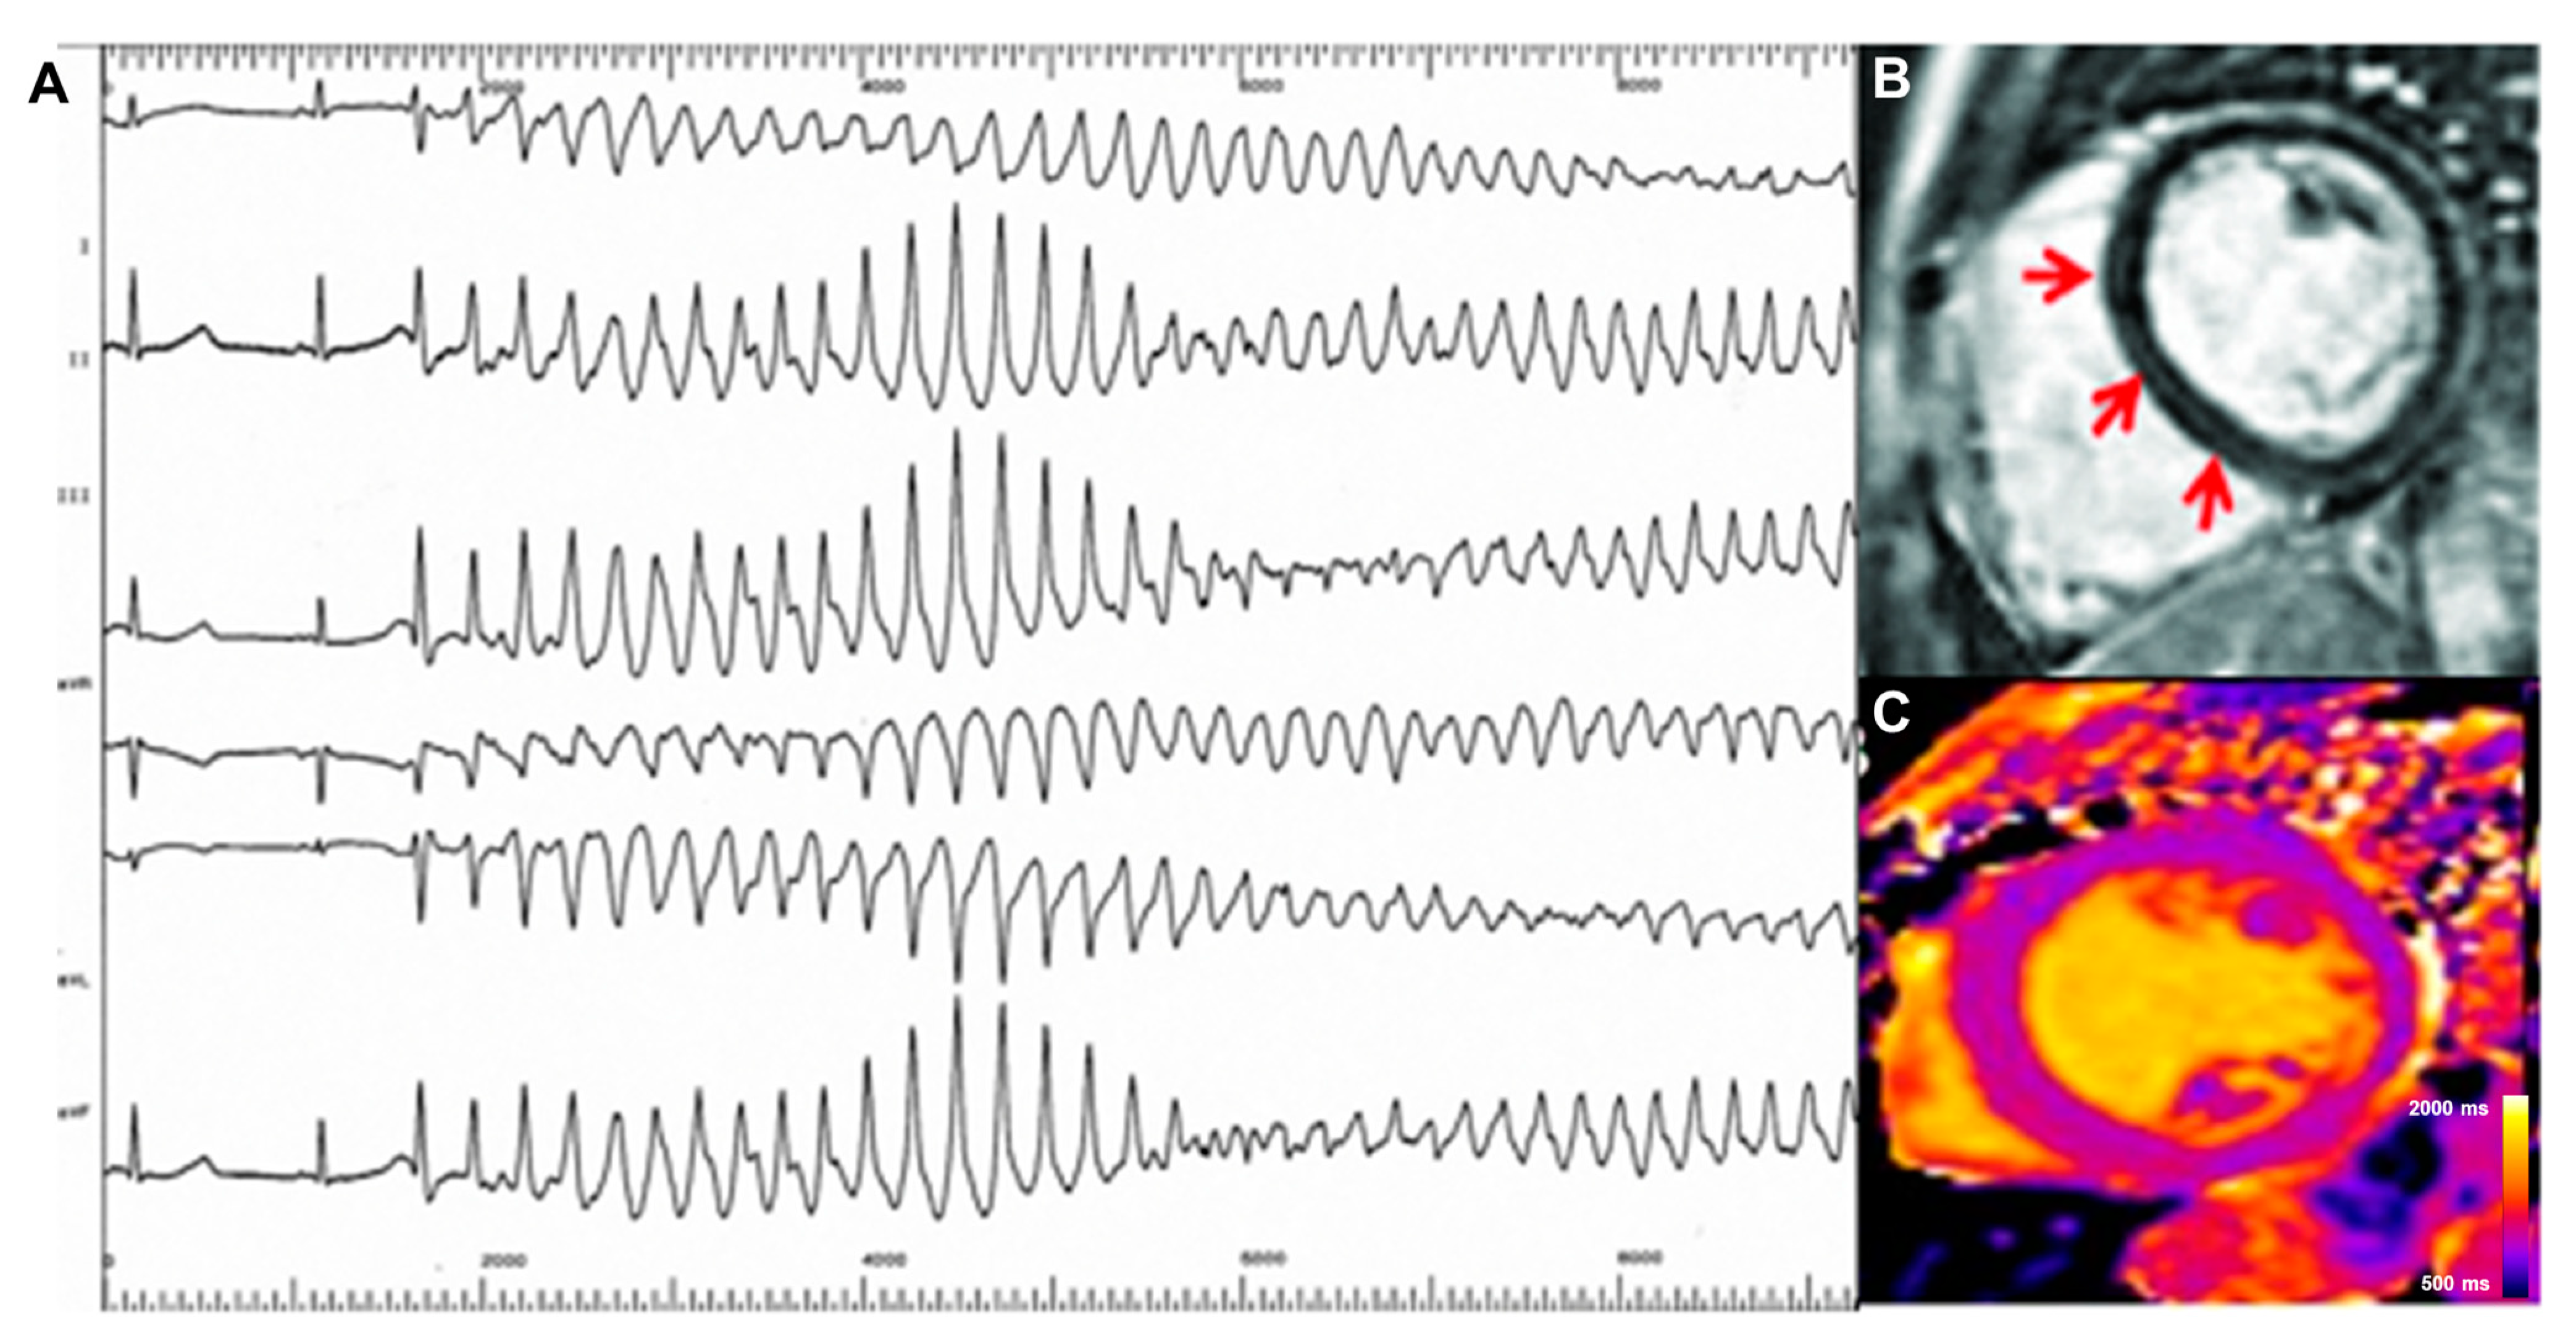

- Gil, K.E.; Truong, V.T.; Zareba, K.M.; Varghese, J.; Simonetti, O.P.; Rajpal, S. Parametric mapping by cardiovascular magnetic resonance imaging in sudden cardiac arrest survivors. Int. J. Cardiovasc. Imaging 2023, 39, 1547–1555. [Google Scholar] [CrossRef] [PubMed]